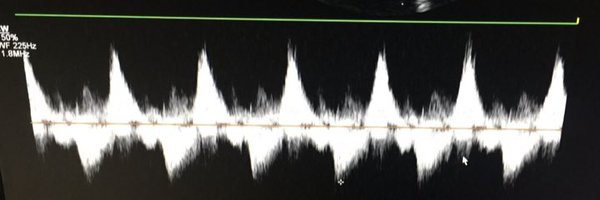

A patient with advanced cardiac amyloidosis. PW Doppler of the hepatic vein is obtained in the subcostal view. What is the finding?